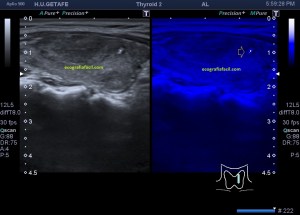

Lo primero, reconoce siempre la normalidad para poder identificar anormalidad. En la imagen 1 tienes una imagen normal de ambos lóbulos tioideos en un corte axial (nos sirve para repasar anatomía básica), en la imagen 2 un corte longitudinal de uno de los lóbulos con su vascularización típica. Bien guarda en tu cabecita estas dos imágenes y ponte en modo concentración para descubrir los cambios semiológicos en el caso de la paciente referida con anterioridad.

1

2